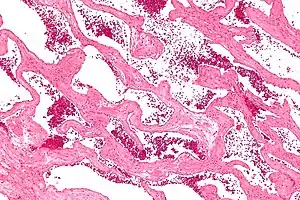

Micrograph of a cavernous liver hemangioma. H&E stain.

Cavernous hemangiomas can arise nearly anywhere in the body where there are blood vessels. They are sometimes described as resembling raspberries because of the appearance of bubble-like caverns. Unlike capillary hemangiomas, cavernous ones can be life-threatening and do not regress.